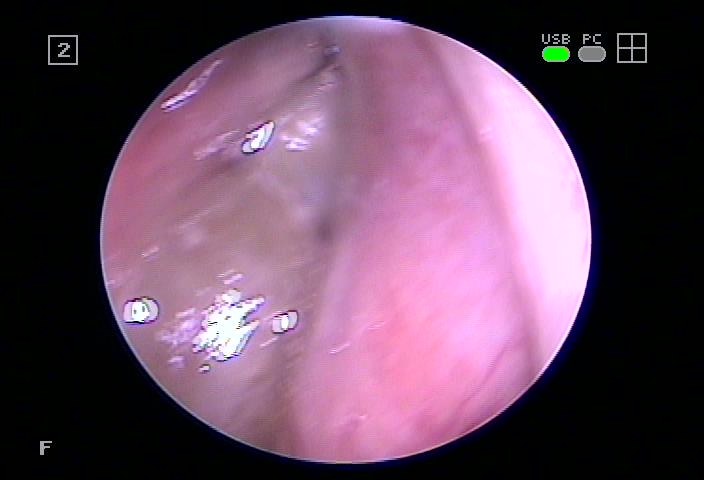

저희 병원에서는 비강 내 안쪽에 있는 내부의 고름을 제거하고 기관지의 건강을 유지할 수 있도록 도와드리고 있었습니다.

본원에서는 3분간 실시되는 점막재생치유를 통해 개개의 기능을 원활하게 회복시켜 면역력 증진과 함께 누적된 농도를 제거하고 섬모의 기능을 향상시켜 노폐물 배출이 충분히 이루어지도록 도와드렸습니다.